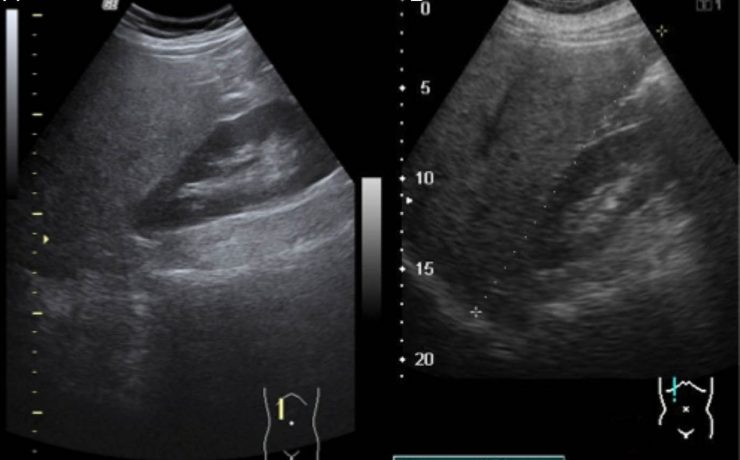

Escrito por Irene Arnanz González en 2014, hace la descripción de una paciente de 94 años quien ingresó a la consulta médica por prurito e ictericia con examen físico sospechoso por lo que se indicó ultrasonido de vías biliares con resultado de vesícula con pared gruesa de hasta 1cm de